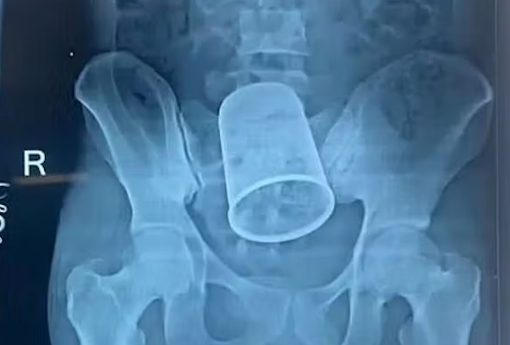

Lægerne fra Patna Medical Collage Hospital blev mildest talt chokeret efter at have undersøgt en 22-årig mand.

Lægerne fik med et samme undersøgt manden, der havde klaget over voldsomme mavesmerter – men da blev de mødt af et chokerende syn.

De kunne således bekræfte, at den 22-årige mand havde en 14 centimeter lang stålkop siddende i hans endetarm.

Stålkoppen havde blokeret for afføringen, hvorfor han altså blev ramt af de voldsomme mavesmerter.